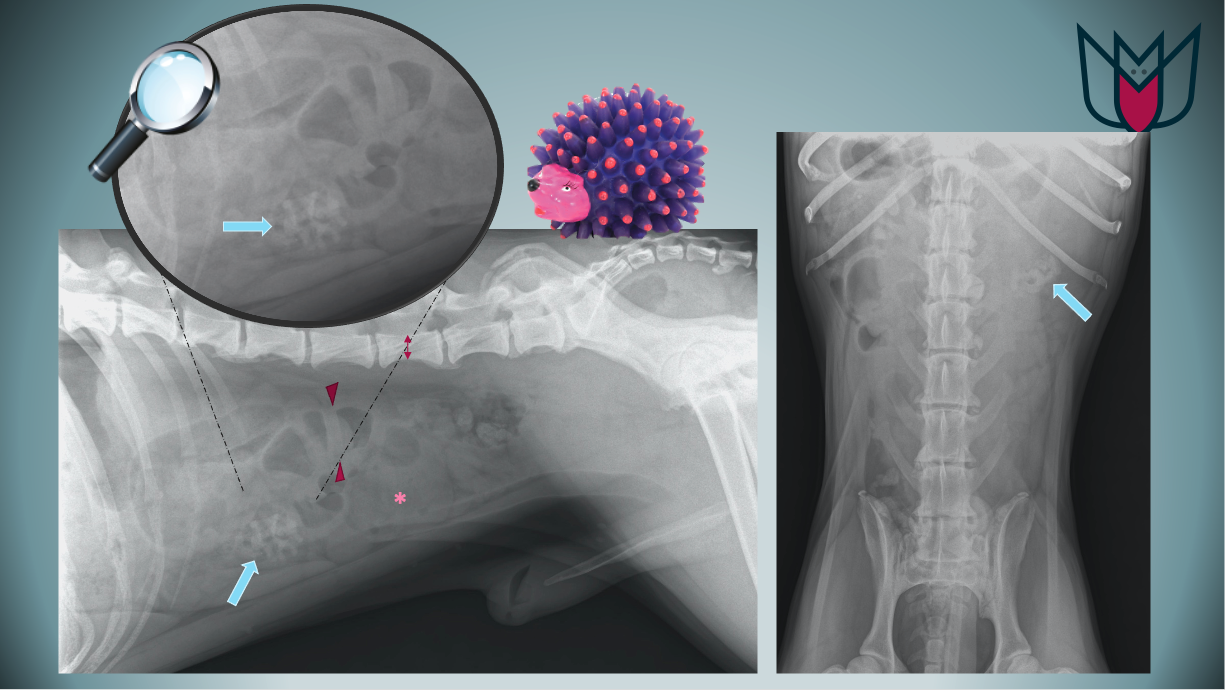

Les vomissements de sang chez les chiens, aussi appelés "hématémèse", peuvent être provoqués par une irritation de l'estomac ou des intestins, une rupture de la paroi de l. Les vomissements de votre chien contiennent du sang ? D'où provient ce sang et comment réagir ? L'hématémèse chez le chien peut avoir diverses origines.

Sang et glaires dans les selles du chien PHOTOS de sang dans les selles du chien. Notez que, dans la plupart des cas, l'hématémèse relève d'une urgence vétérinaire absolue, il est donc essentiel de ne pas perdre trop. Si vous voyez que votre chien vomit du sang, conduisez-le immédiatement chez le vétérinaire qui pourra ainsi déterminer les causes du saignement-car les facteurs qui peuvent provoquer ce problème sont nombreux